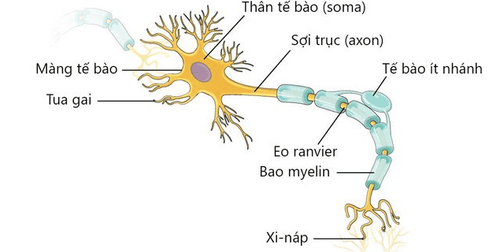

Như vậy có thể thấy, tế bào thần kinh là tế bào dài nhất trong cơ thể con người. Nơ-ron là đơn vị cơ bản cấu tạo nên hệ thần kinh của hầu hết các loài động vật và là thành phần quan trọng bậc nhất của não, có khả năng cảm ứng, phát ra xung động thần kinh và dẫn truyền xung điện.

Ước tính có khoảng 100 tỷ nơron trong não con người. Nơron là những tế bào dài nhất trong cơ thể người, có độ biệt hóa cao nên mất đi trung thể và khả năng phân chia, tuy nhiên nơron có khả năng tái sinh lại phần cuối của sợi trục trong những trường hợp bị thương tổn.